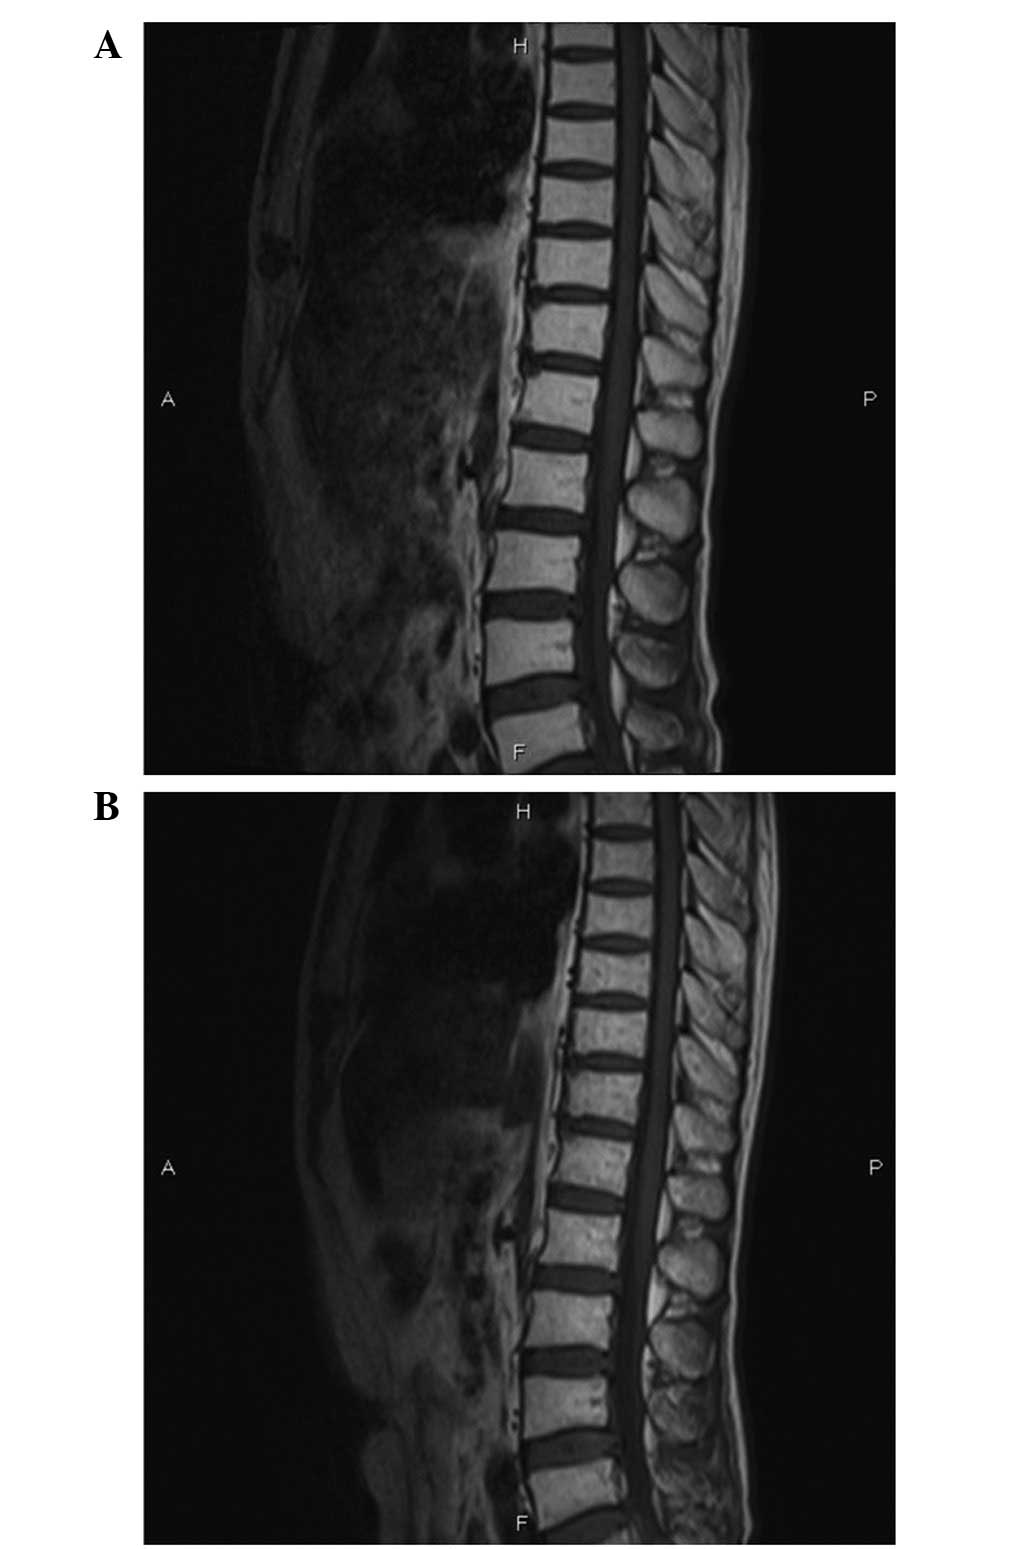

2013. After experiencing CNSL remission, the patient was given IT

had recovered. Repeat MR imaging showed no infiltration in the

spinal cord (Fig. 3A). The patient

However, in April 2013, the patient developed a

sudden onset of paraplegia and urinary retention again. Repeat MR

imaging of the spine and brain revealed no evidence of disease

progression, spinal cord compression or brain metastasis (Fig. 3B). A repeat CSF examination during